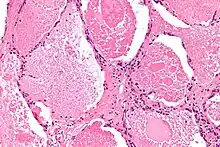

Micrograph of pulmonary alveolar proteinosis, showing the characteristic airspace filling with focally dense globs referred to as chatter or dense bodies. H&E stain.

Lung washings or tissue for histopathologic analysis are most commonly obtained using bronchoalveolar lavage and/or lung biopsy.[12] Characteristic biopsy findings show filling of the alveoli (and sometimes terminal bronchioles) with an amorphous eosinophilic material, which stains strongly positive on PAS stain and the PAS diastase stain. The surrounding alveoli and pulmonary interstitium remain relatively normal.[13] Electron microscopy of the sample, although not typically performed due to impracticality, shows lamellated bodies representing surfactant.[14] An alternative diagnosis with similar histomorphologic findings is Pneumocystis jirovicii pneumonia.[14]

Lung washings characteristically yield a fluid which is "milky"composition. Under the microscope, samples show 20-50 micrometer PAS-positive globules on a background of finely granular or amorphous PAS-positive material. There is typically a low numbers of macrophages and inflammatory cells (although this is variable).[13][14]